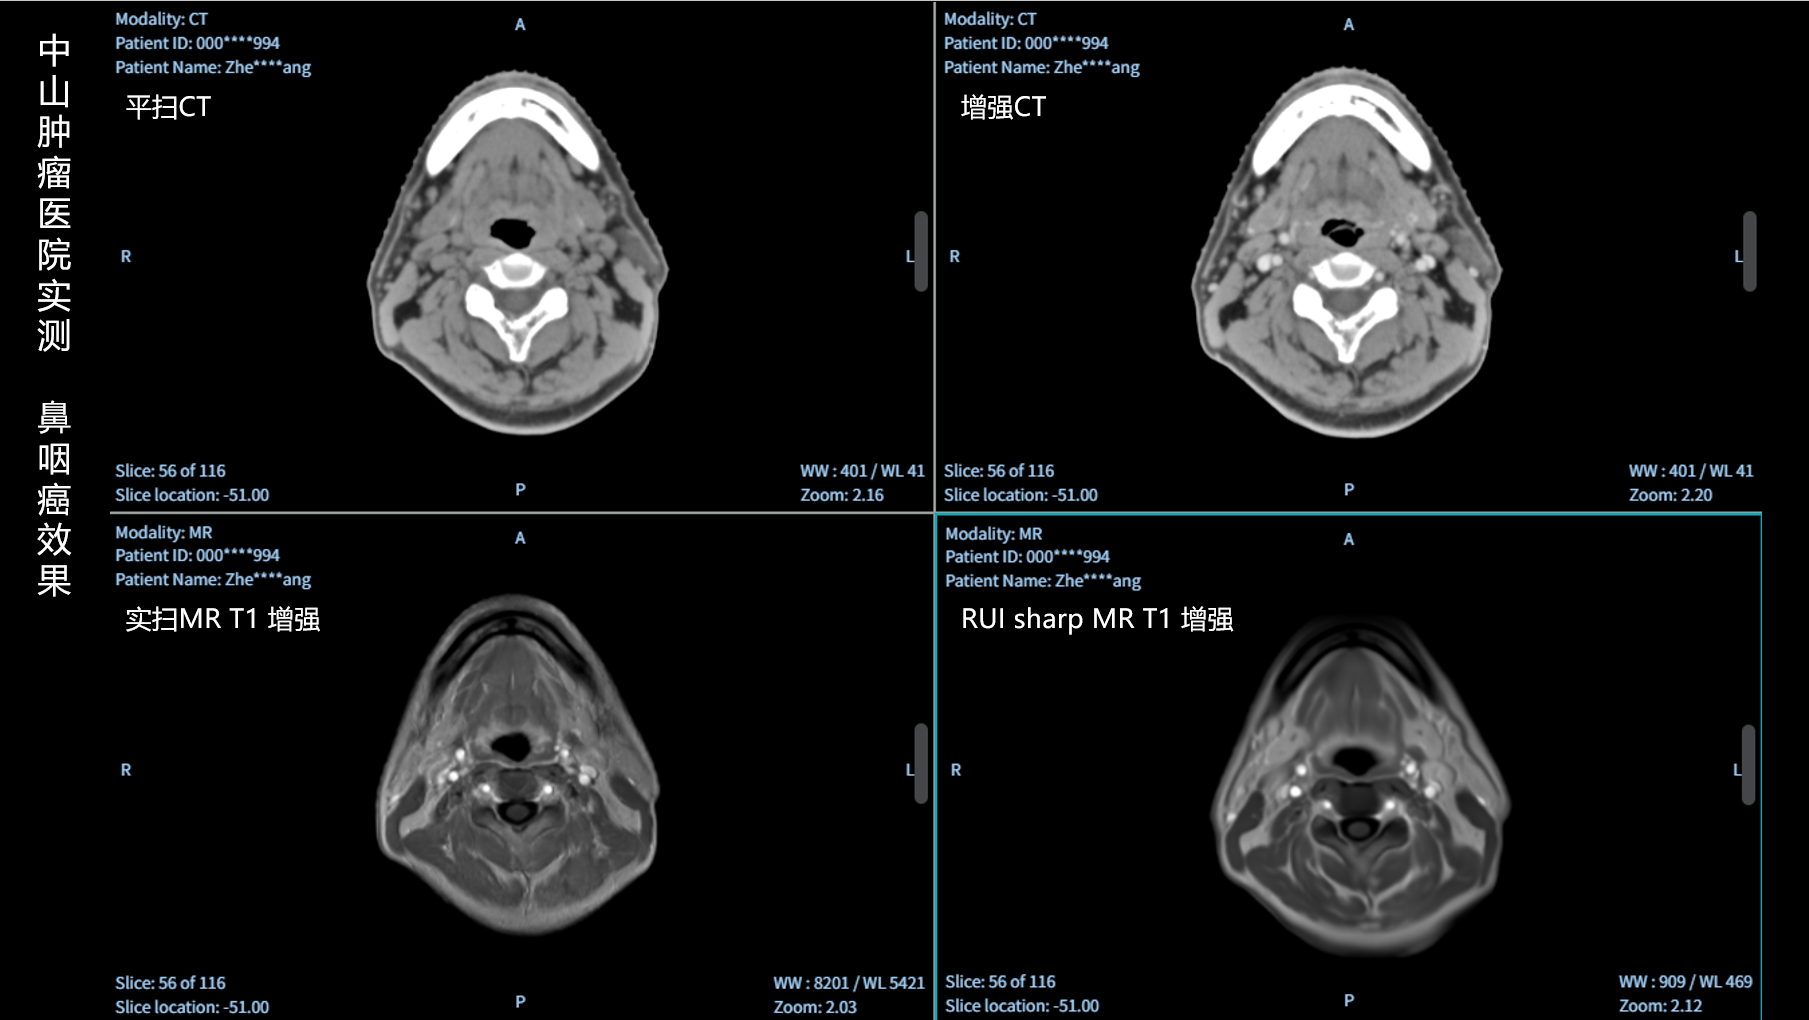

RUI sharp H(锐影)可在不依赖MRI的前提下,显著提升头部CT图像的软组织分辨率,为临床提供更高质量的辅助信息,尤其适用于MRI资源受限或较难配准的头颈部放疗感兴趣区勾画场景。

可大幅提高头部CT影像软组织分辨率,使肿瘤和周边器官显示更清晰,为放疗靶区勾画提供参考。

无需图像配准,CT和锐影图像同源,可匹配、叠加、"淡入淡出"显示。

实测效果